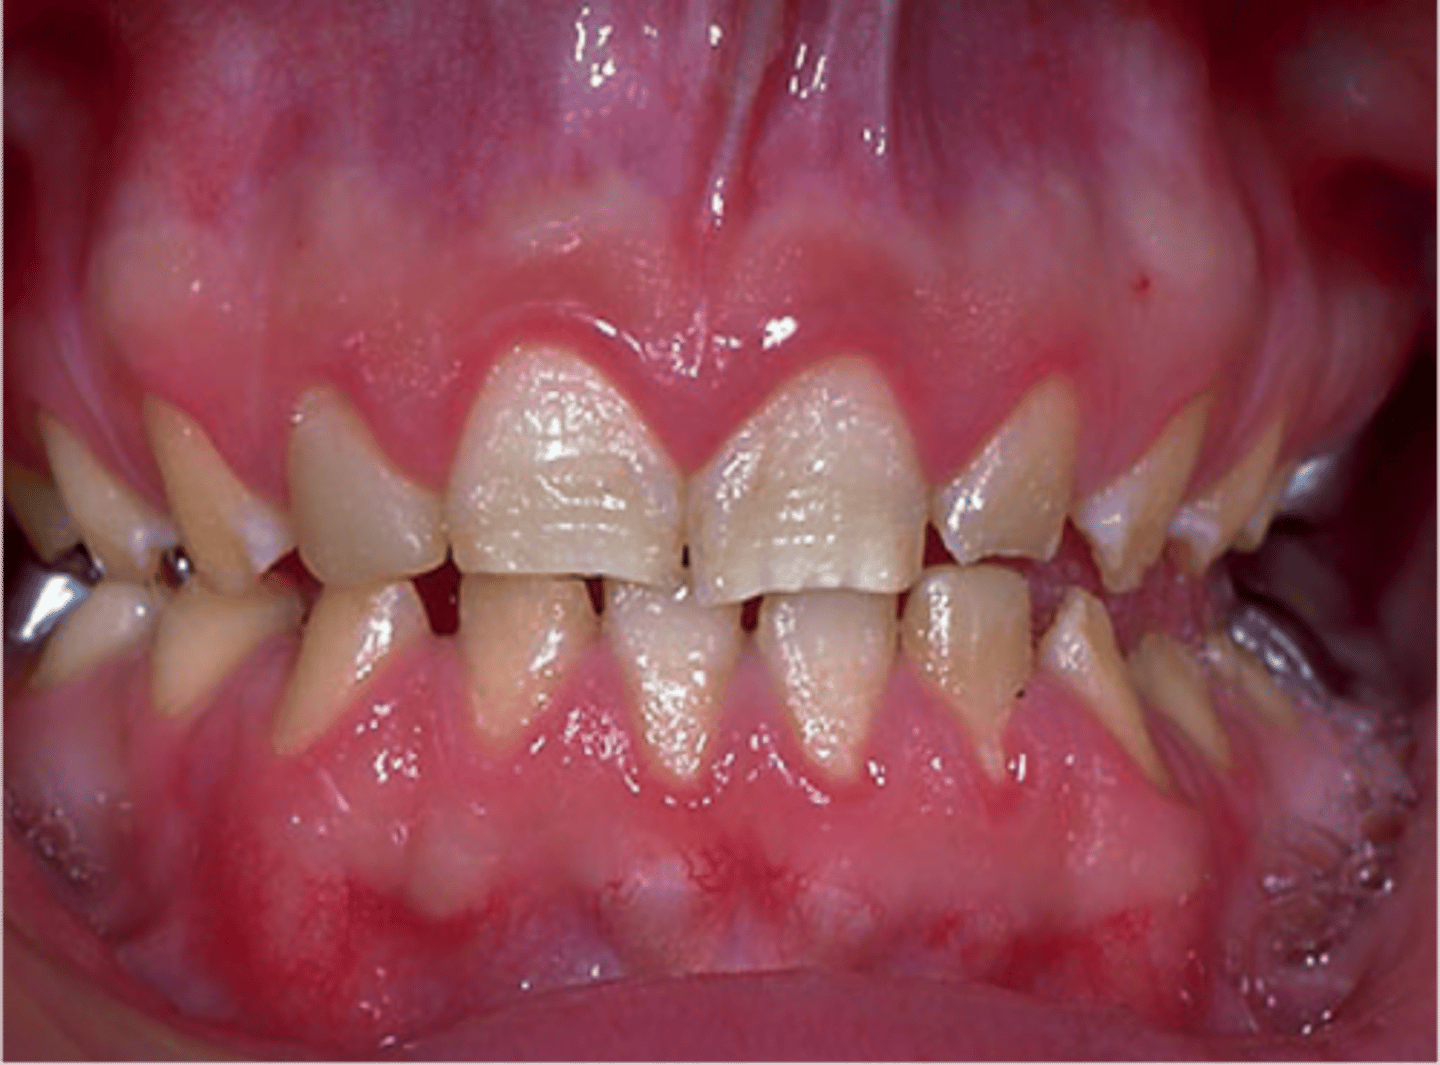

Papillon-Lefèvre Syndrome

At about what age does an individual with Papillon-Lefèvre Syndrome develop a gingivoperiodontal inflammatory process.

1.5 - 2 years of age

Hyperkeratinization of the palms and soles and marked hyperkeratinization of labial and lingual gingiva is known as:

Focal Palmoplantar and Gingival Hyperkeratosis